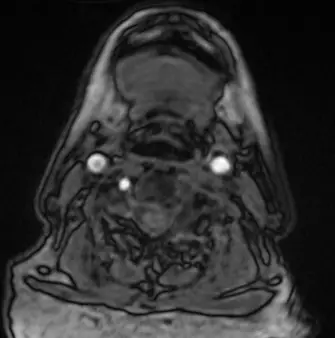

此圖為頸部的 2D TOF MRA 橫斷面(Axial)原始影像(Source image)。

- 在影像左側(患者右側),可見明亮的高訊號圓點,分別代表右側的頸動脈(Carotid artery)以及後方的右側椎動脈(Right vertebral artery)。

- 在影像右側(患者左側),可見明亮的左側頸動脈。

- 然而,在患者左側椎動脈的解剖位置上,卻呈現完全沒有訊號(黑色)。題目特別強調「每一張影像」左邊椎動脈都沒有訊號。